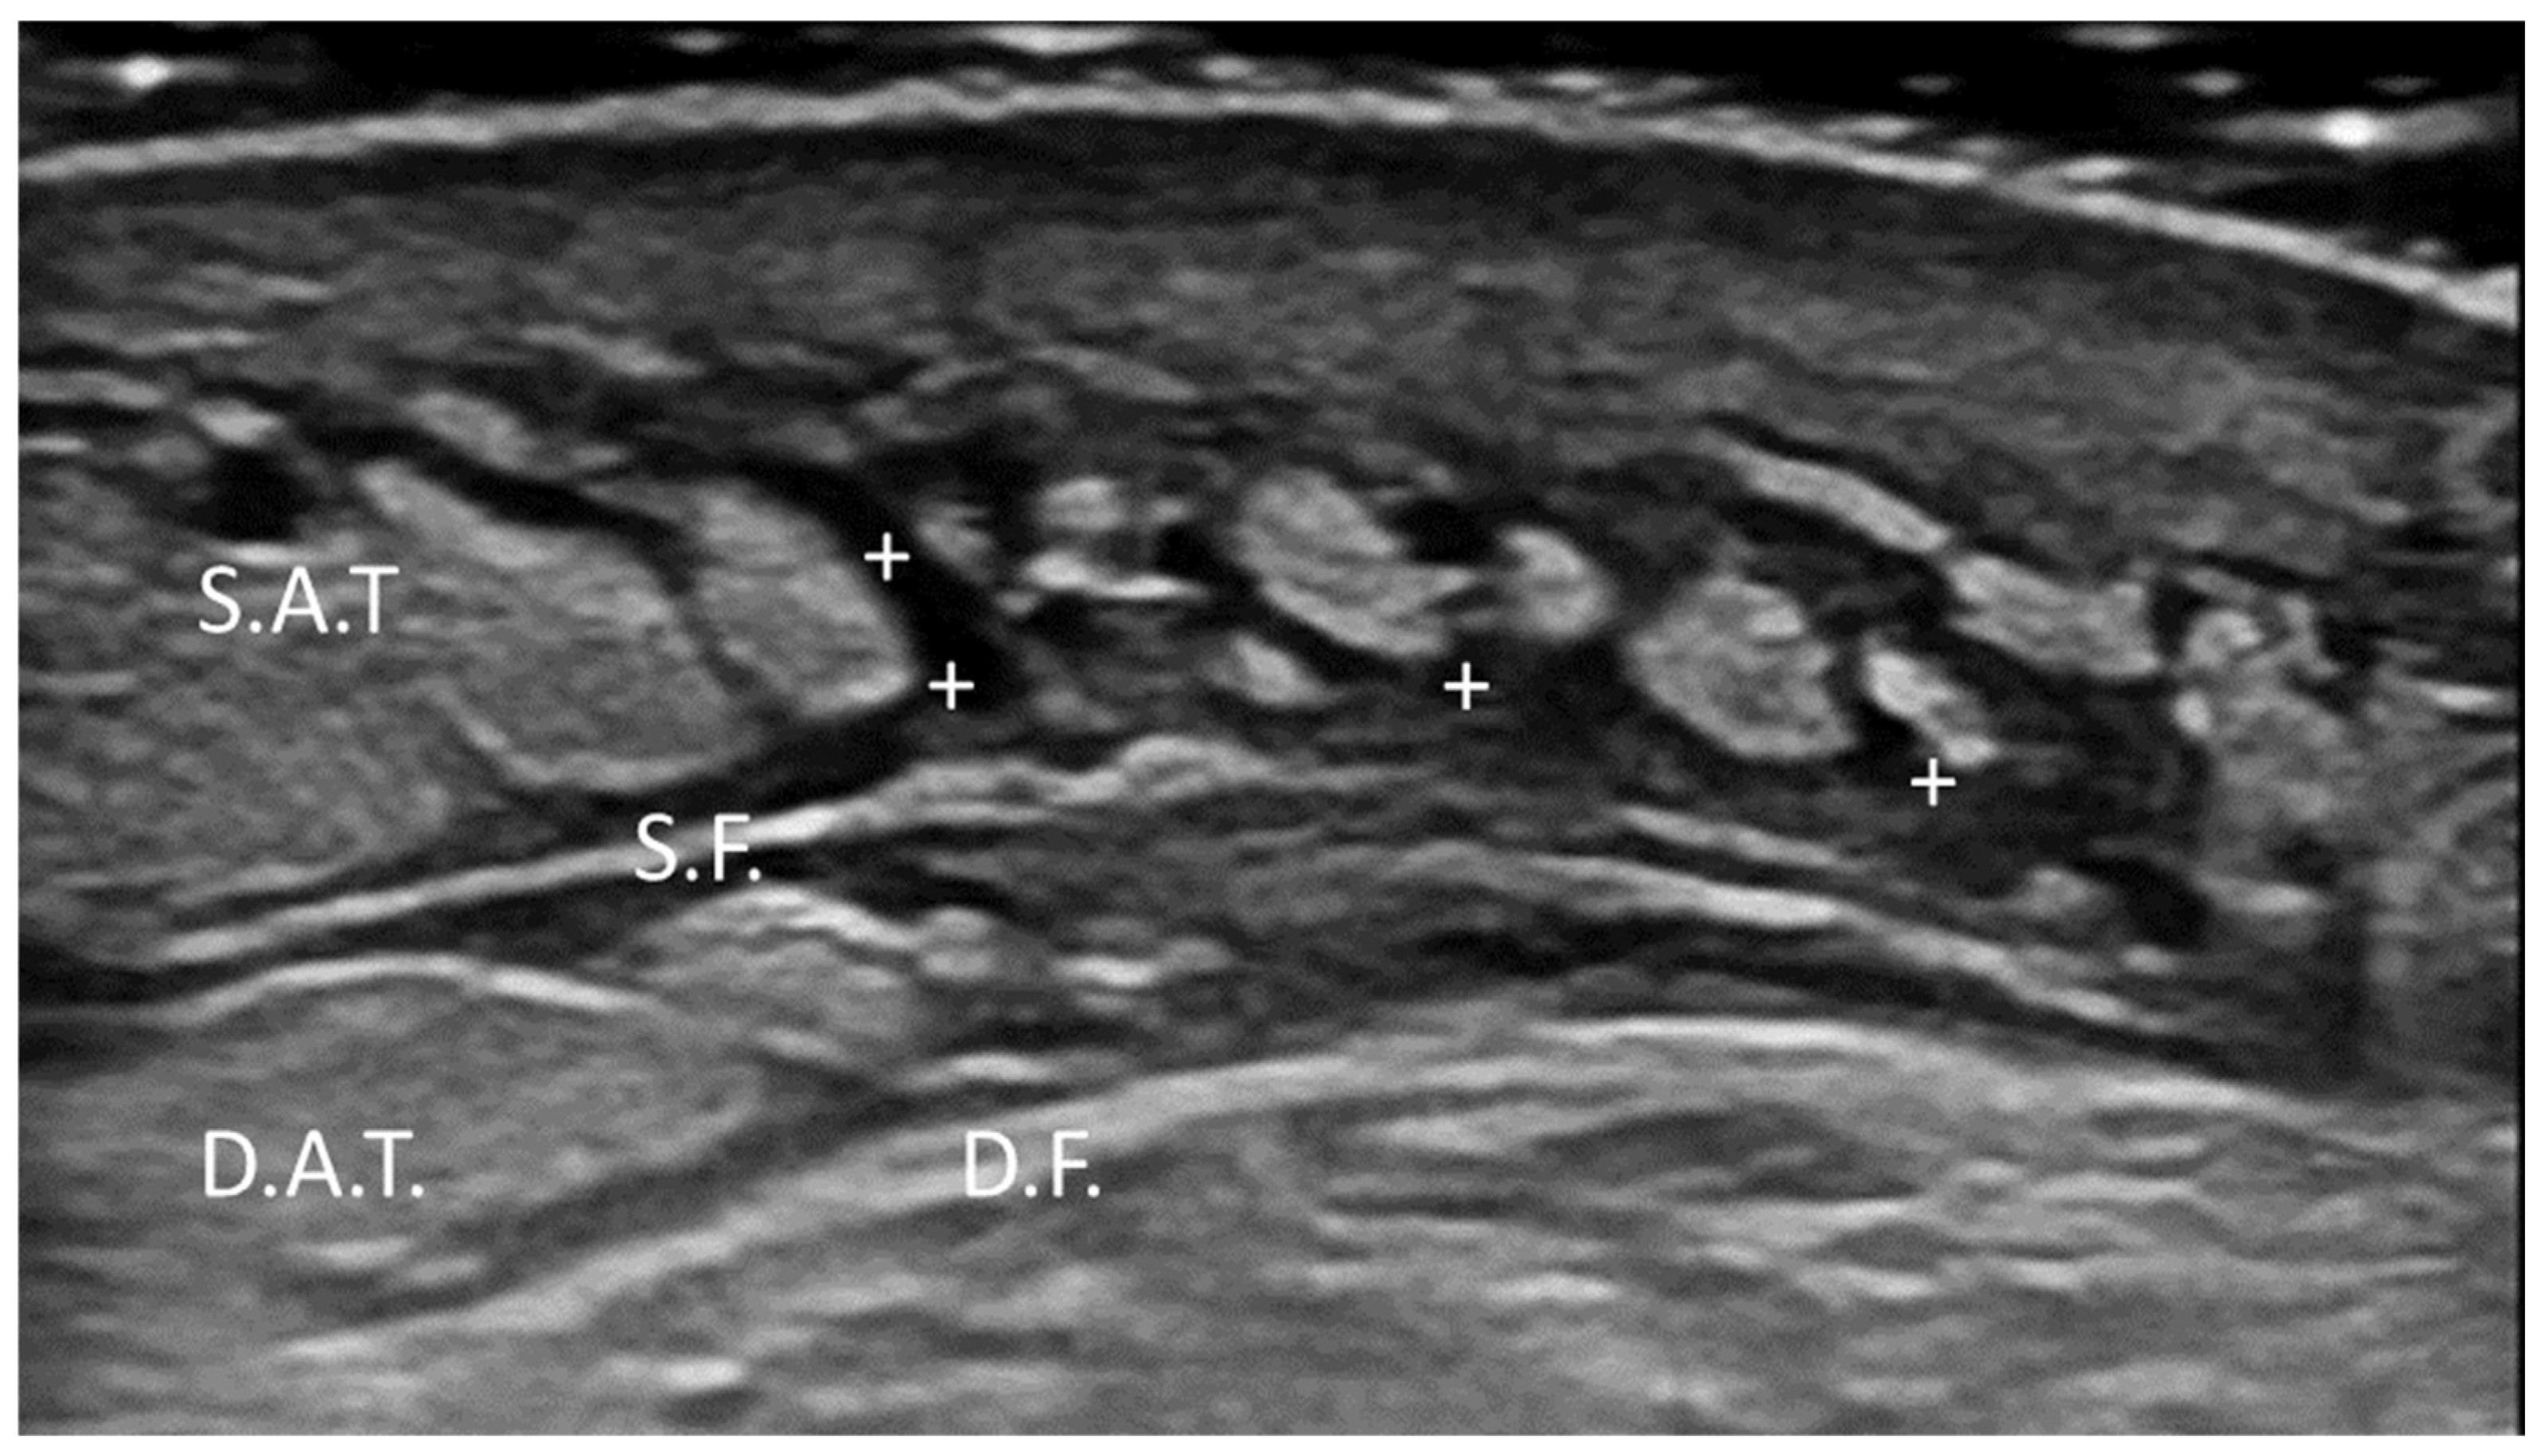

3.5.2. Morel–Lavallée Lesion (MLL)